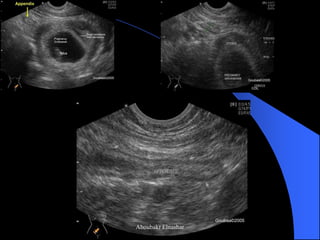

Scan RLQ with increasing pressure

to push bowel loops away

Empty cecum of gas& fluid

Sonographic Criteria

Noncompressible

> 7mm diameter

<6mm rules out appendicitis

Mural thickening > 3mm

Presence of appendicalith

Acute appendicitis